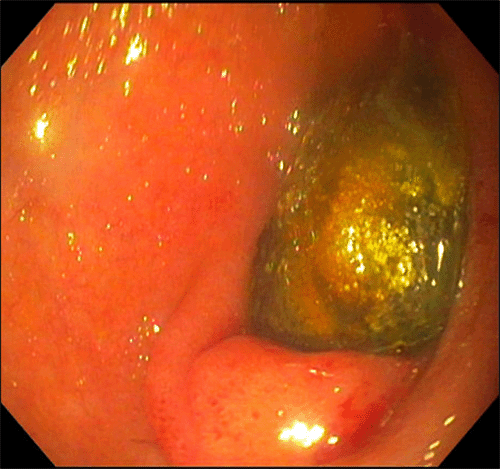

Figure 3. Endoscopic Identification of Duodenal Gallstone. Published with Permission

Gallstone impacted within the second portion of the duodenum, as identified via upper endoscopy

The gastroenterology team attempted esophagogastroduodenoscopy (EGD) to visualize the obstruction. However, the cholecystoduodenal fistula could not be visualized due to the size and immobility of the stone. Attempts to dislodge the stone or place a Roth net were unsuccessful.

Following consultation with general surgery for gastric outlet obstruction, possibly due to Bouveret syndrome, the patient consented to an exploratory laparotomy with potential bowel resection and open cholecystectomy. Surgical intervention proceeded within 24 hours. While no stone was initially palpable in the proximal small bowel, further exploration revealed a single palpable stone lodged within the jejunum. A 2 cm longitudinal enterotomy was created using electrocautery to access the stone, which was then successfully delivered from the bowel lumen (Figure 3). The enterotomy was closed in an interrupted fashion with 3-0 silk sutures. Additionally, a falciform flap was fashioned and positioned in the right upper quadrant near a visualized cholecystoduodenal fistula. The patient tolerated the procedure well, was extubated in the operating room, and taken to the postanesthesia care unit (PACU) in excellent condition. Her postoperative recovery was uneventful, and she was discharged home four days after the procedure.